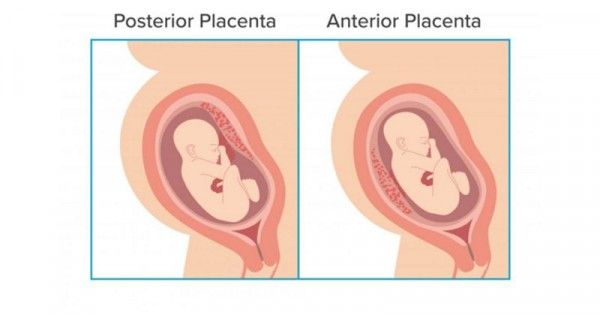

Perhatikan Letak Plasenta Janin Saat Hamil

Perhatikan Letak Plasenta Janin Saat Hamil

Kenali Cara Membaca Hasil USG Untuk Tahu Kondisi Bayi - Ibupedia

Kenali Cara Membaca Hasil USG Untuk Tahu Kondisi Bayi - Ibupedia

Perkembangan Dan Posisi Janin Yang Perlu Diperhatikan | Arla Indonesia

Perkembangan Dan Posisi Janin Yang Perlu Diperhatikan | Arla Indonesia